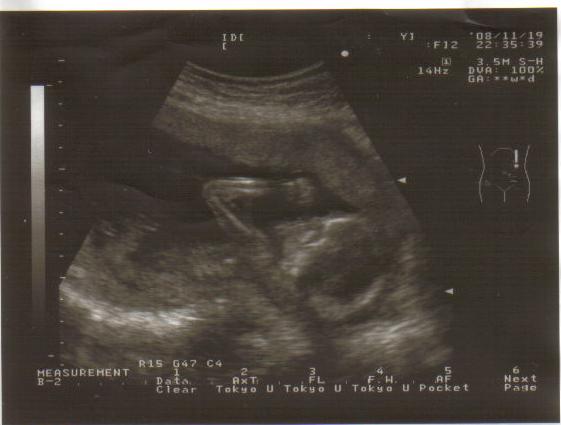

a to nasz synek :-)

to nasz synek :-) w 18 tygodniu + 2 dni

• bazin.jpg

bazin.jpg

142,2 KB · Wyświetleń: 255